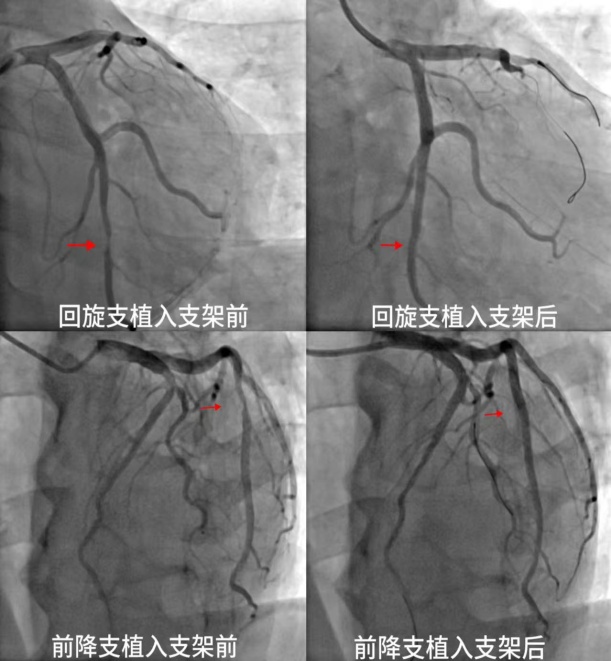

十堰人醫(yī)巧筑“心”橋,迅速打通生命通道

日前,患者王先生(化姓)因持續(xù)胸悶到十堰市人民醫(yī)院就診,該院心內(nèi)科2病區(qū)主任吳三五博士帶領團隊經(jīng)過精確診斷,迅速安排手術打通嚴重狹窄的心臟血管,幫助王先生恢復健康。根據(jù)王先生的病情,吳三五博士團隊經(jīng)心電圖、心臟彩超等檢…

• “生命通道”重獲生機,十堰人醫(yī)成功救治復雜冠心病危重患者

“生命通道”重獲生機,十堰人醫(yī)成功救治復雜冠心病危重患者

近日,一面繡著“醫(yī)術精湛品德優(yōu),服務熱忱如親人”的鮮紅錦旗,在十堰市人民醫(yī)院心內(nèi)科2病區(qū)徐徐展開,見證了又一段技術與溫度并重的健康故事。患者王先生(化名)因持續(xù)胸悶癥狀來到十堰市人民醫(yī)院就診。通過心電圖、心臟彩超等一系列…